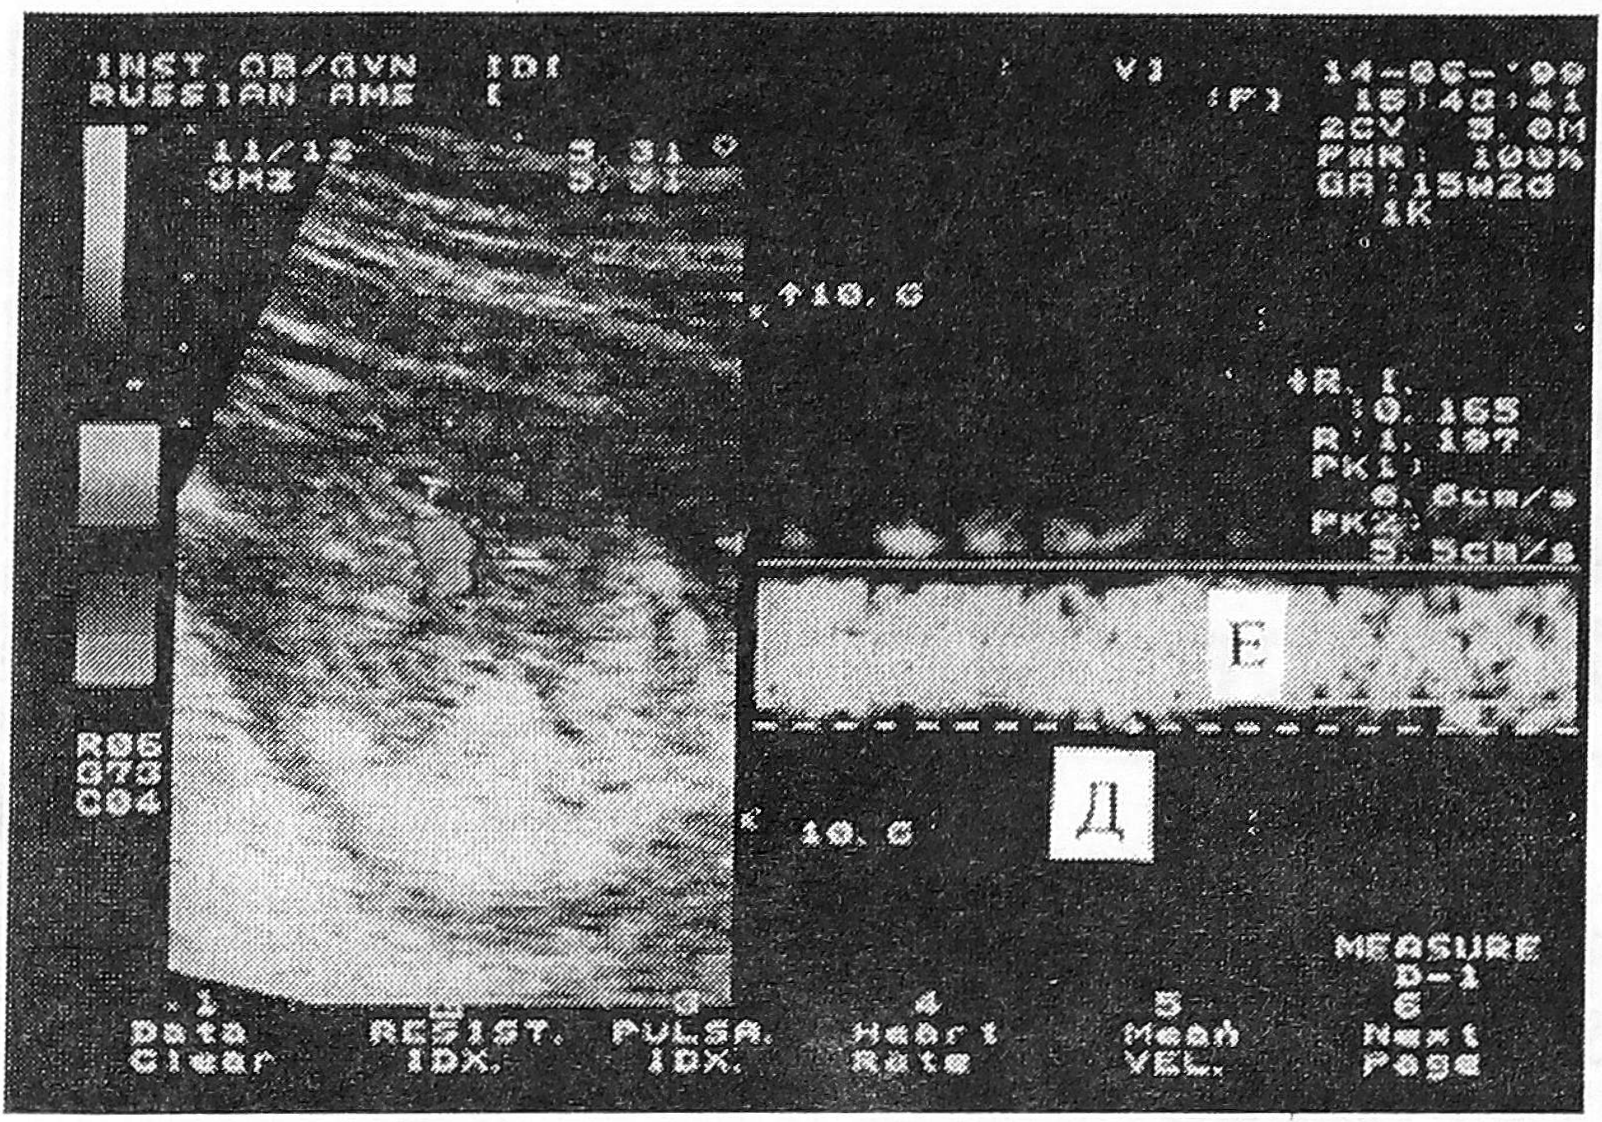

Согласно результатам нашего исследования основные изменения кровотока в вене пуповины наблюдаются в течение первого и начале второго триместра беременности. Процесс его формирования включает несколько этапов, которые характеризуются сменой условий циркуляции крови в пупочной вене. При этом процессы становления кровотока в пупочной вене совпадают с периодом формирования низкорезистивных плацентарных сосудов. Так, в первом триместре беременности в пупочной вене определяется пульсирующий кровоток, обусловленный влиянием работы сердца плода (рис.3). В начале второго триместра пульсация в пупочной вене постепенно исчезает. После 16-й недели беременности оксигенированная кровь из плаценты к плоду поступает с постоянной скоростью, что свидетельствует о переходе на качественно новый уровень становления пуповинной циркуляции.

Рис. 3. Допплерограмма пульсирующего кровотока в вене. Д — максимальная скорость кровотока, Е - минимальная скорость кровотока.

Постоянный спектр кровотока в пупочной вене является важным критерием стабильности гемодинамических процессов в фетоплацентарной системе во второй половине нормально развивающейся беременности.